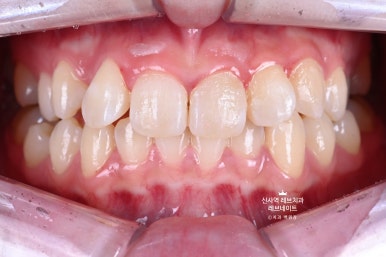

Before & After

지금 보면 이제 자연스러워 보이는 이 모습이

원래는 이런 부정교합의 모습이었다는 것!

비교해보면 더 확연히 마음에 닿으실 거에요.

뭔가 가지런히 정돈되서, 환자분도 저희들도 만족하고 뿌듯했던 케이스였습니다!